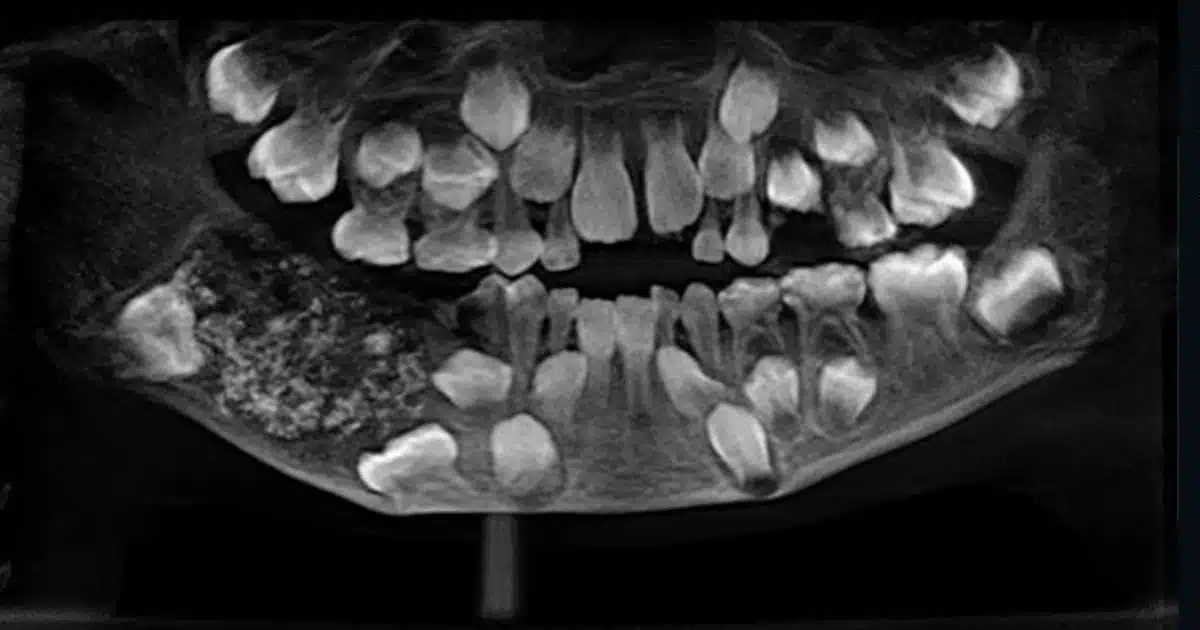

En Inde, un enfant de 7 ans a été hospitalisé en urgence à cause de fortes douleurs à la mâchoire. Le garçon a été admis en juin dans un hôpital de Chennai, ville située dans le sud de l'Inde. Il souffrait d'un gonflement important près des molaires à droite de la mâchoire inférieure. Afin de retirer le surplus, les médecins ont donc décidé de l'opérer. On vous parlait aussi de ce père de famille qui était mort alors qu'il avait simplement mal aux dents. Les médecins se sont alors rendu compte que le petit garçon avait énormément de dents ! Ce n'est qu'à la fin de l'opération qu'ils ont vraiment pu déterminer le nombre de dents exact. Pendant près de 5 heures, ils ont compté un par un les morceaux d'émail allant de 0,1 millimètre à 15 millimètres.

Et il y en avait 526 ! Le petit garçon souffrait d'une maladie rare appelée odontoma composite. La cause de cette maladie n'est pas connue, mais elle pourrait être liée à un problème génétique ou des facteurs environnementaux tels que des radiations. Heureusement, tout va bien, le garçon a désormais des dents en très bonne santé.